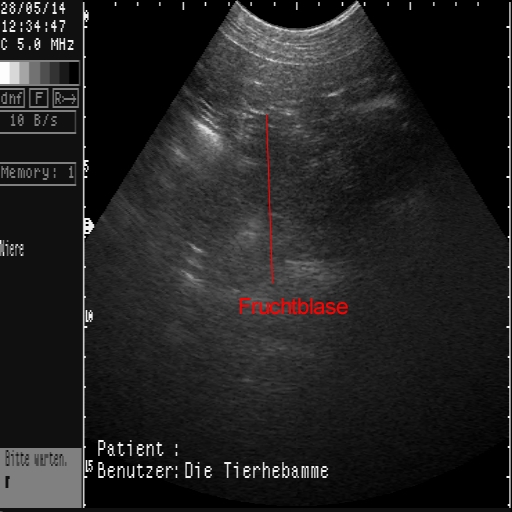

Das sind die ersten Ultraschallbilder vom 28.05.2014!

Es hat wirklich geklappt!

Die Tier-Hebamme hat 9 kleine Fruchtblasen gezählt...!!!

In den ersten Tagen änderte sich nichts an Mayas Verhalten, das wir nicht auch schon von Scheinschwangerschaften kannten. Deswegen waren wir wahnsinnig auf den ersten Besuch der Tier-Hebamme gespannt, die uns am 28.05.2014 endlich besuchte, um einen Ultraschall zu machen!

Wir haben die lange Wartezeit kaum ausgehalten und dann doch irgendwie geschafft! Mit einem positiven Ergenis, wie man an den Bildern sehen kann. Sage und schreibe neun kleine Fruchtblasen waren für das (geübte) Auge der Hebamme zu erkennen - wir haben nix gesehen....  Uns dafür aber unglaublich gefreut!!!!